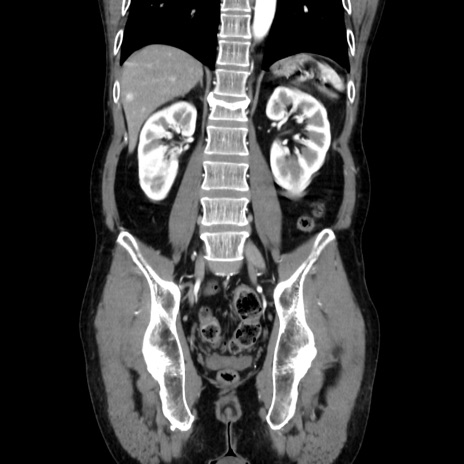

症例37(冠状断像)

【症例】40歳代 男性

【主訴】腹痛

【現病歴】4時間ほど前に電車に乗車中に臍部上より腹痛出現。徐々に増悪し起立困難となり、救急外来受診。生ものは数日食べていない。今朝お雑煮を食べた。

【身体所見】BT 36.8℃、BP 117/84mmHg、HR 91/min、SpO2 97%、苦悶様、腹部:臍上部広範囲圧痛あり、反跳痛±

【データ】WBC 8100、CRP 0.03